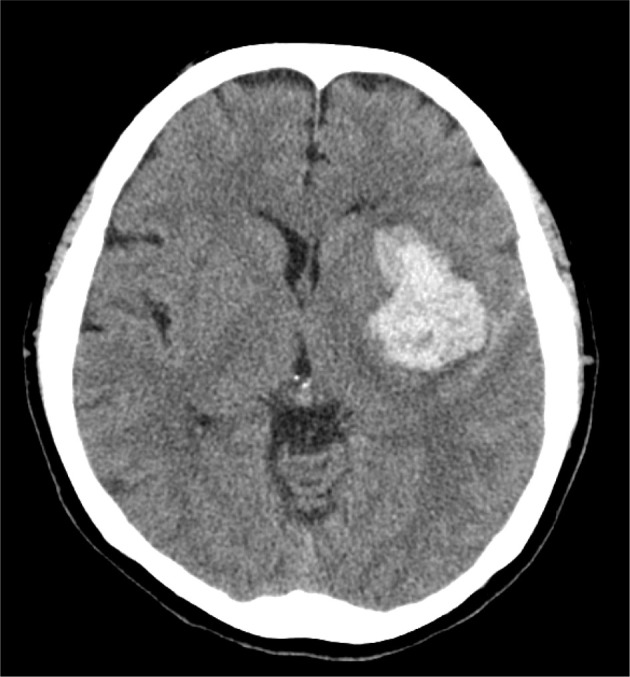

【目的】本研究旨在探讨体重支撑的地上训练对严重脑卒中偏瘫患者步态恢复的影响。【参与者与方法】参与者为一名40多岁的女性,中风后严重偏瘫。采用单例ABAB设计。第一和第三阶段采用标准物理治疗,第二和第四阶段采用物理治疗结合体重支撑的地面训练。采用步行速度、Timed Up and Go测试、运动功能的Brunnstrom恢复阶段(BRS)和Fugl-Meyer评估(FMA),以及日常生活活动(ADL)的运动功能独立性测量(m-FIM)来评估体重支撑的地面训练的效果。[结果]步行速度从进站时的0.26 m/s提高到第一期的0.37 m/s,第二期的0.58 m/s,第三期的0.45 m/s,第四期的0.50 m/s,出站时使用t拐杖步行速度达到0.40 m/s。m-FIM评分从入院时的20分稳步上升到出院时的74分,而BRS和FMA的改善微乎其微。[结论]体重支撑型地上训练可提高重度脑卒中偏瘫患者的行走能力、功能表现和自理能力。

[Purpose] This study aimed to examine the effect of body weight-supported overground training on gait recovery in a patient with severe stroke-induced hemiplegia. [Participants and Methods] The participant was a woman in her 40s with severe hemiplegia following a stroke. A single-case ABAB design was employed. Standard physiotherapy was provided in the first and third phases, while physiotherapy combined with body weight-supported overground training was administered in the second and fourth phases. Walking speed, Timed Up and Go test, Brunnstrom recovery stage (BRS) and Fugl-Meyer Assessment (FMA) for motor function, and motor-functional independence measure (m-FIM) for activities of daily living (ADL) were performed to assess efficacy of body-weight-supported overground training. [Results] Walking speed improved from 0.26 m/s at admission to 0.37 m/s in the first phase, 0.58 m/s in the second phase, 0.45 m/s in the third phase, and 0.50 m/s in the fourth phase, reaching 0.40 m/s with a T-cane at discharge. m-FIM scores increased steadily from 20 points at admission to 74 points at discharge, while BRS and FMA showed minimal improvement. [Conclusion] Body weight-supported overground training may enhance walking ability, functional performance, and ADL independence in patients with severe stroke-induced hemiplegia.